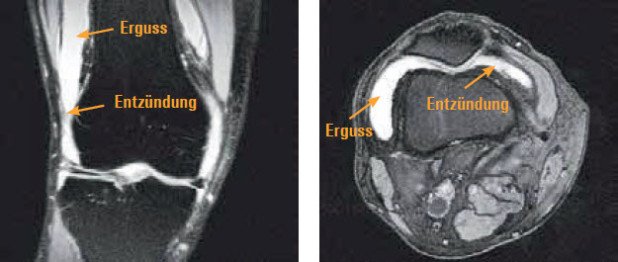

Links: Frontaler Schnitt

Rechts: Horizontaler Schnitt: Deutlicher Erguss, zottenartige Veränderungen der Gelenkmembran im Sinne einer chronischen Entzündung (Synovitis); geringe Knorpelveränderungen im seitlichen Kompartiment